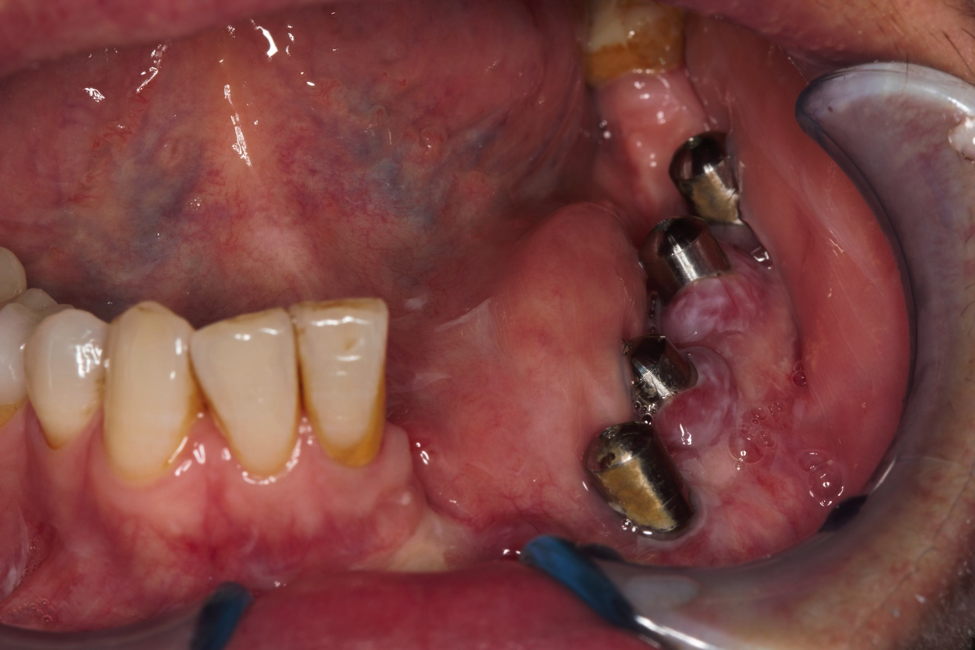

This patient had to undergo jaw surgery and he lost a lot of his teeth and bone. We managed to place implants in his bottom jaw and restore him with an implant-supported denture to give him his lost teeth, bone, and tissue back. This was a very challenging case from start to finish!